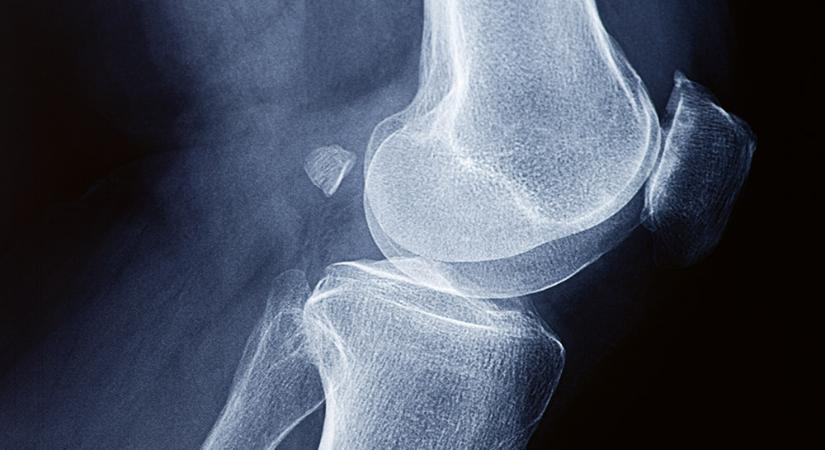

A GenuForm AI mesterséges intelligenciával oldja meg a térdporc-átültetések legnagyobb problémáját: a donorporc pontos illesztését a páciens csontfelszínéhez. Ez az áttörés nemcsak hatékonyabbá teszi a beavatkozást, hanem lehetővé teszi, hogy egyetlen donortól akár több beteg is új esélyt kapjon a fájdalommentes mozgásra. Térdeket ment az MI A térdporc-kopás világszerte milliókat érintő betegség, és az […]